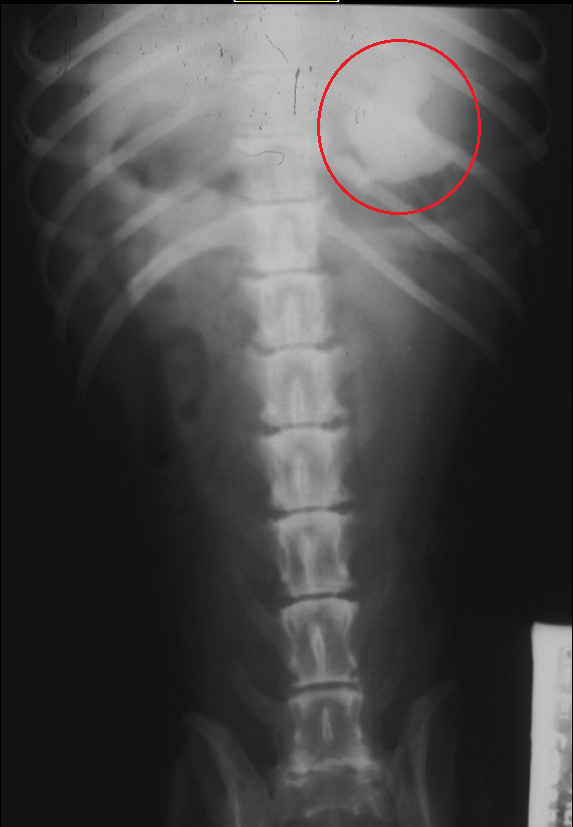

For one of our GI Radiology labs, we kept seeing ducks in various parts of the digestive tract

Like in this one:

Patient exhibited signs of vomiting and anorexia. Of course she did! She had a fucking duck in her stomach!